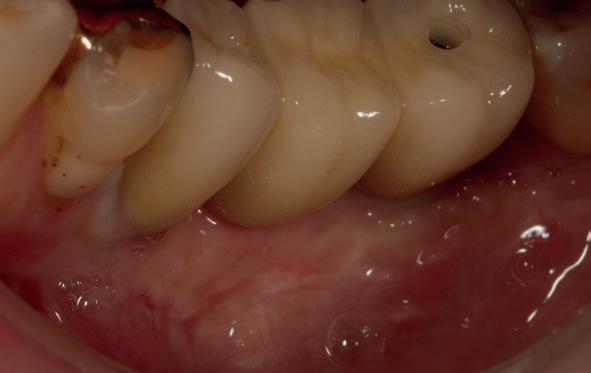

Na 4 weken intra-orale scan voor de etsbrug en kleurbepaling bij de technicus

• Plaatsen van de etsbrug met een composietcement

Voordat er gescand kon worden voor een etsbrug, werd een studiemodel vervaardigd om met de technicus te overleggen of er voldoende ruimte was voor 2 centrale incisieven in de mesio-distale zin en of er voldoende ruimte was in occlusie voor de vleugels van de etsbrug. Er hoeft enkel nog aan de 12 en 22 pala-

tinaal geslepen te worden als er geen 1,5 mm ruimte voor de vleugels behaald kan worden. De ruimte was op de dunste plekken 1 mm, dus een kleine preparatie in de 12 en 22 palatinaal was nodig. Omdat de kaak volledig afgevlakt was en dun was geworden, kunnen de dummies van de etsbrug enkel op de kaak “gelegd worden”, maar daarbij zijn er geen papillen en staat de cervicale rand van de dummies net voor de kaak. Een esthetisch resultaat kan daarmee niet behaald worden. Daarom is een aanvulling van de zachte weefsels in de breedte nodig, als het creëren van een emergence profile, waarbij het oogst alsof de gebitselementen uit het weefsel vertrekken.

18. Etsbrug frontbeeld

19. Etsbrug palatinaal